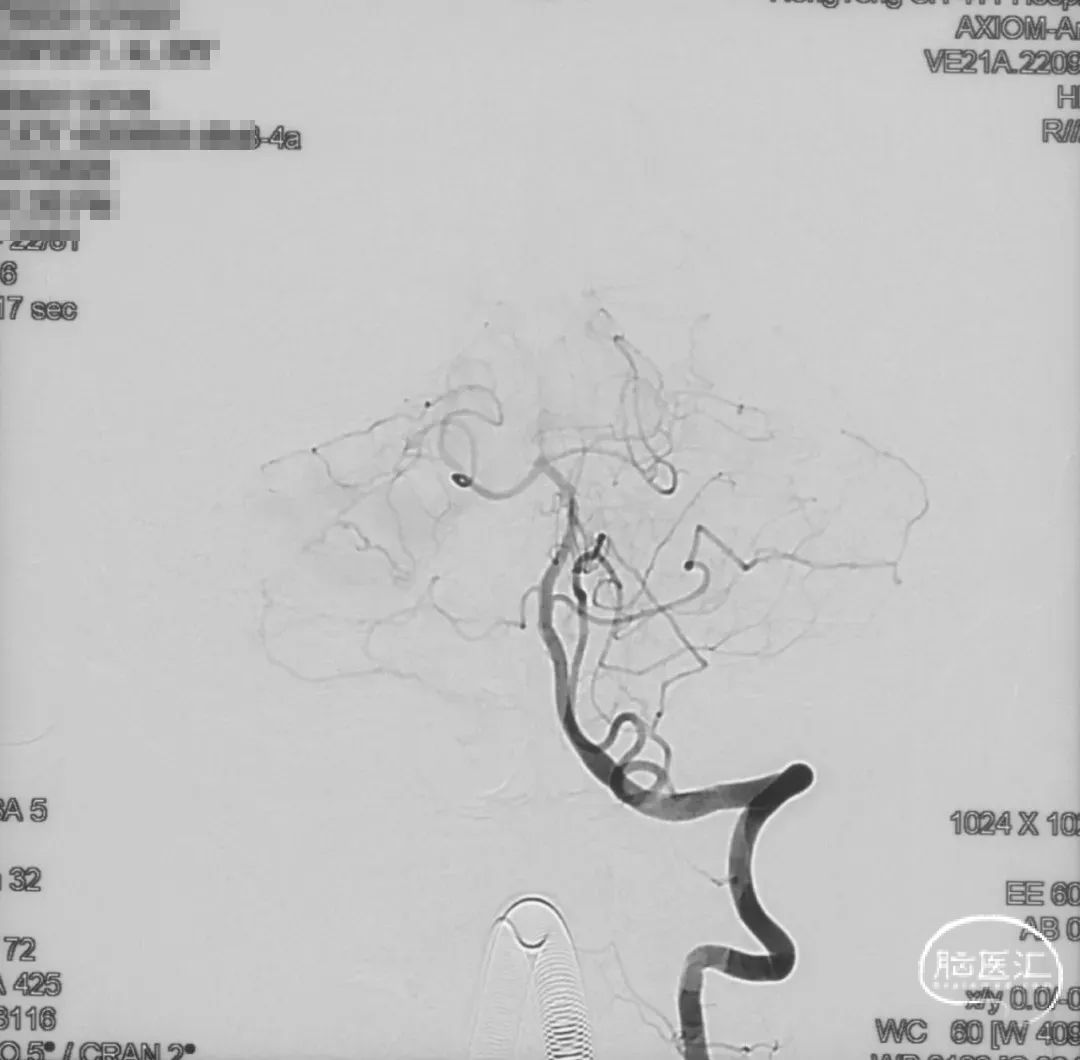

双侧颈外、颈内动脉正侧位造影瘘口均不显影

双侧椎动脉造影未见瘘口显影,可见广泛皮层静脉瘀滞

患者后循环造影可见皮层静脉广泛淤滞样改变,遂予以抗凝药物治疗。

术后9m

右侧颈内动脉造影未见瘘口显影及静脉早显

右侧颈外动脉造影未见瘘口显影及静脉早显

左侧椎动脉造影未见瘘口显影及静脉早显